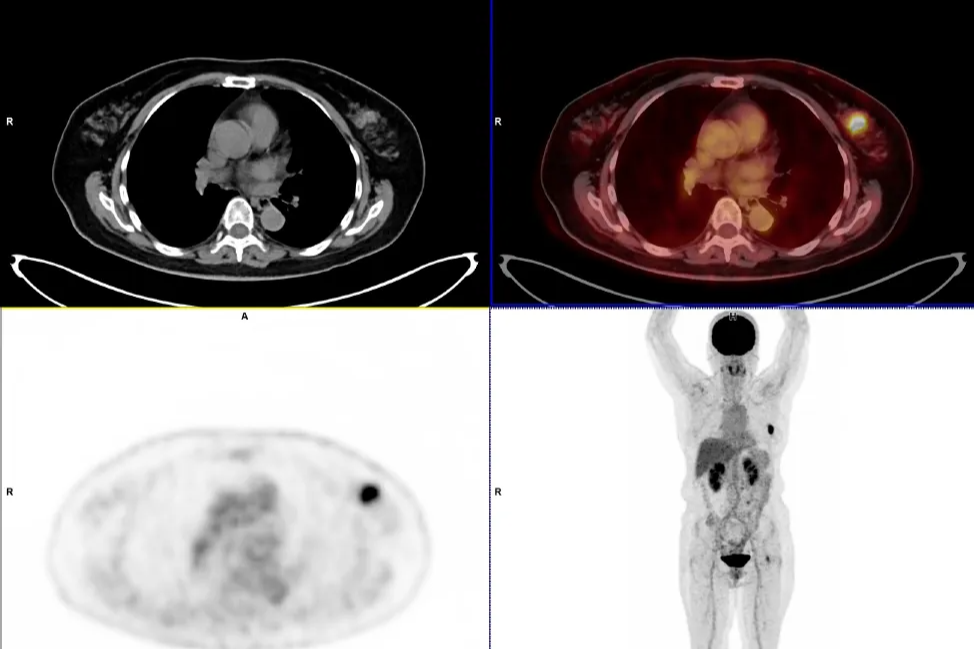

淋巴瘤治疗显成效!PET/CT 见证病灶「大撤退」

「牵一发而动全身」—以为是肺的事,PET/CT 揭秘—全身淋巴瘤